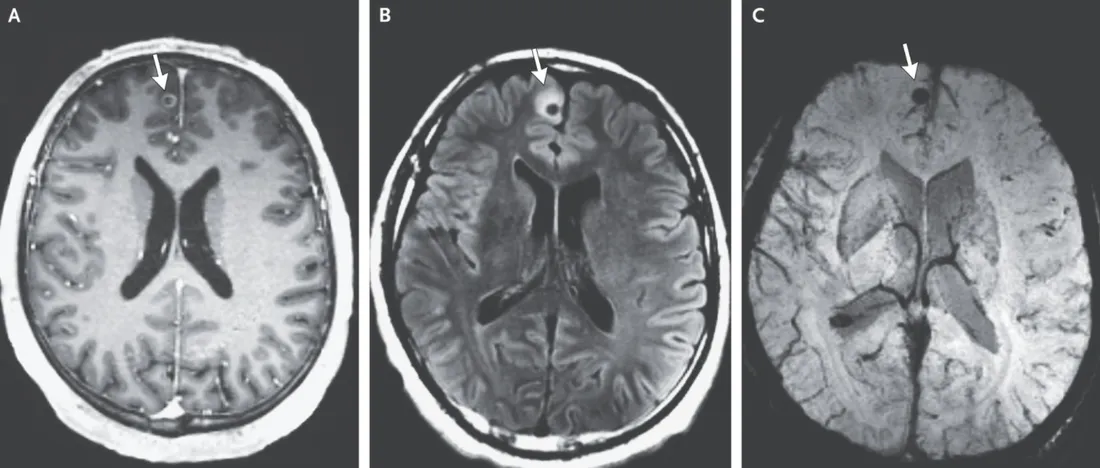

Peu de temps après, le bon diagnostic tombe enfin. De nombreuses lésions cérébrales sont observées sur l’imagerie et les spécialistes aperçoivent la trace d’« un compagnon indésirable » dans le cerveau du patient : un ténia mort. Le ver solitaire a, en effet, migré dans sa tête, quelques années plus tôt, et a provoqué des kystes larvaires dans différentes parties du cerveau, explique la revue New England Journal of Medecine. On parle alors de neurocysticercose.

Selon plusieurs spécialistes, l’homme, qui a vécu au Guatemala avant d’émigrer vers les Etats-Unis, aurait probablement consommé un plat infecté par un ténia, car de nombreux parasites similaires existent en Amérique latine. « Ce monsieur est un cas atypique, mais pas si rare au final, car le parasite était mort depuis une ou deux décennies. L’infection avait disparu, mais une partie de son cerveau n’avait pas complètement cicatrisé, ce qui provoquait les crises », détaille le Dr. Edward T. Ryan, directeur des maladies infectieuses et co-auteur d’une étude, au Washington Post. Aujourd’hui, l’homme est sorti de l’hôpital et doit suivre un traitement strict pour combattre l’infection.